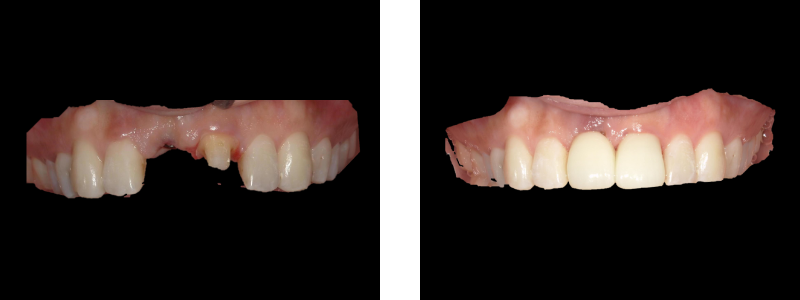

治療内容 右上前歯を抜歯しインプラント埋入

期間 約2ヵ月

費用 385,000円

(インプラント【被せ物、手術代、仮歯含む】275,000円+骨再生、歯肉再生110,000円)

注意点/副作用 外科処置が必要・全身状態によりできない場合がある。